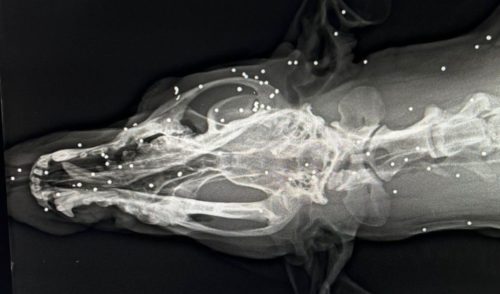

En la madrugada del miércoles pasado una perra recibió un disparo a pocos metros de distancia que le dejó el cuerpo lleno de perdigones. Y todo aconteció en las inmediaciones de la casa de sus dueños en el lugar de Salgueiroas, en Santa Comba.

El que se conoce de los hechos y que pasadas las dos y media de la madrugada, silbaron desde un coche para llamar por la perra y acto seguido ya escucharon un disparo. Cuando llegaron a la altura de la perra la encontraron tirada y llorando. En el lugar donde le dispararon aún hay rastro de los impactos de los perdigones en el cierre metálico. Y donde aún se deja sentir la agresión es en las heridas de la perra, que está aún en tratamiento por la cantidad de perdigones que tiene en el cuerpo.

Así lo explica Mar Carracedo, la veterinaria que la atendió: “Tiene perdigones cómo doscientos en todo lo que es cabeza, extremidades delanteras y cuerpo, por la trayectoria se ve que el disparo fue de cara a la perra”.